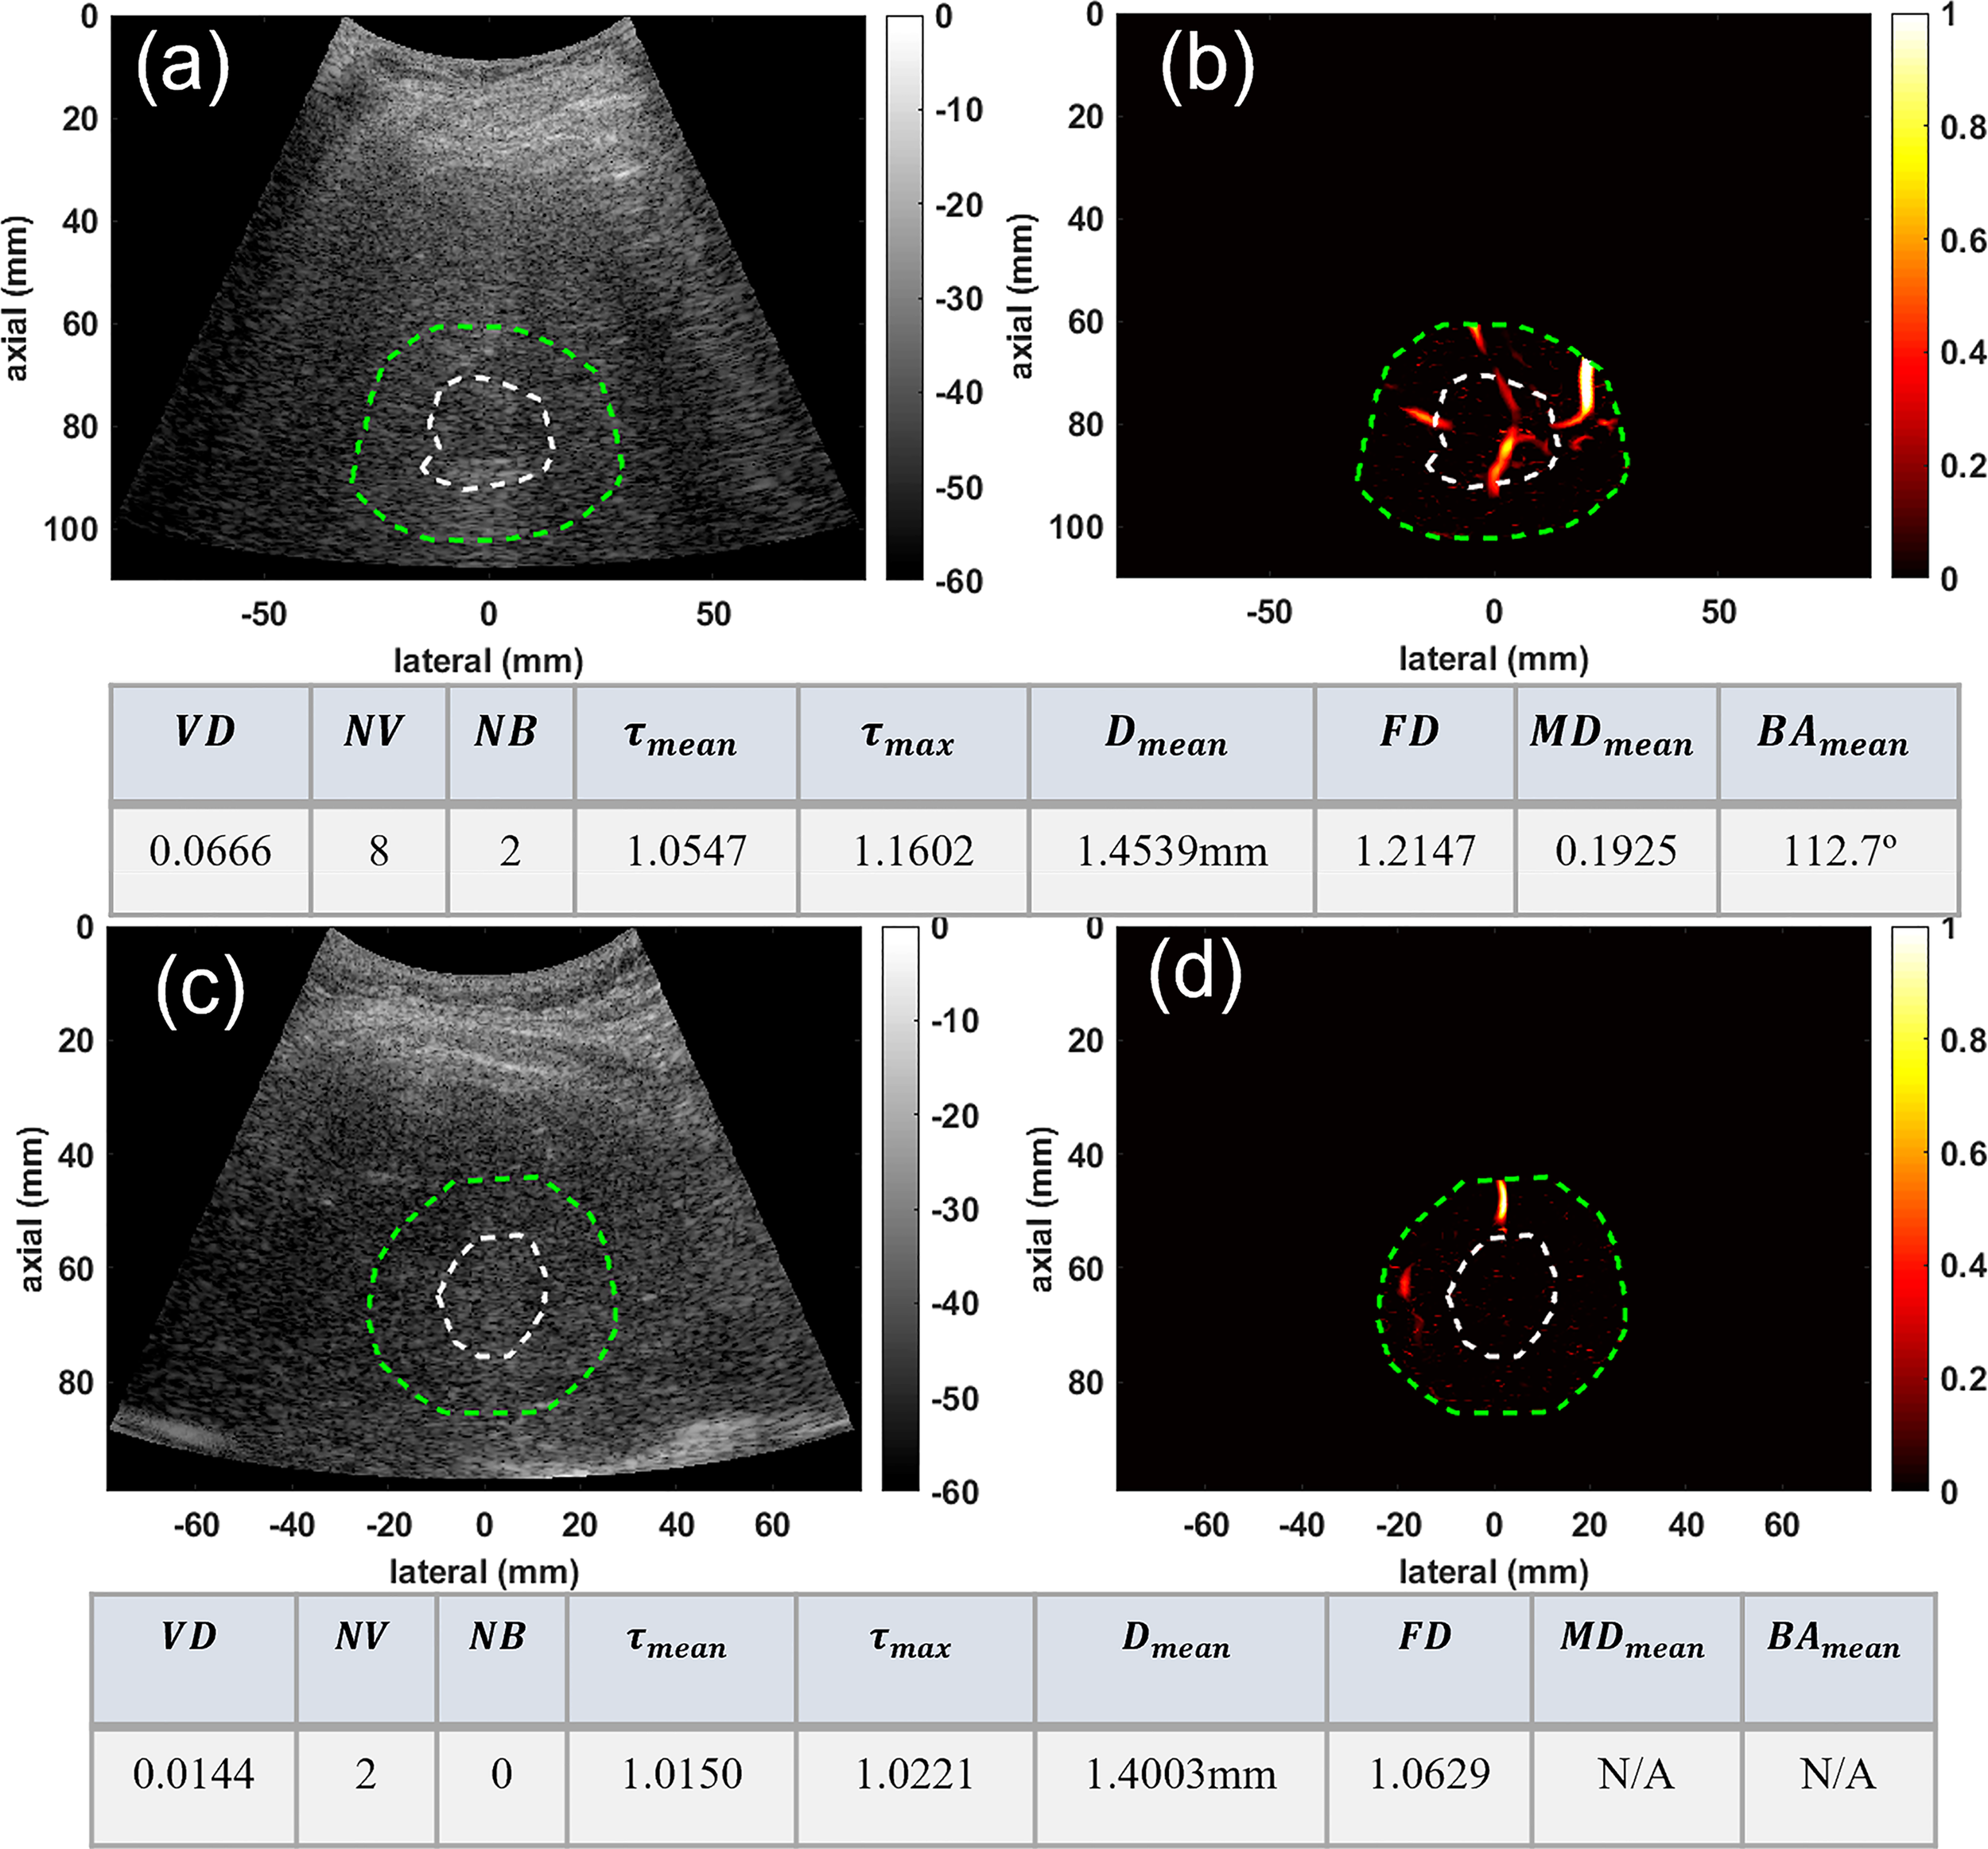

In the second group, the conventional B-mode ultrasound and HMDI images of two deep-seated small liver masses, an HCC and a benign mass, are shown in Figure 3 for visual comparison. This figure depicts the ability of HDMI in visualizing vasculature in and around deep-seated hepatic masses. The B-mode and microvasculature images of a dilated mass mask, centered approximately about 80mm, are shown in Figures 3A, B, respectively. This tumor is confirmed to be HCC. The B-mode and microvasculature images of another dilated mass mask, seated approximately about 90mm in depth, are shown in Figures 3C, D, respectively. This tumor is confirmed to be benign. The corresponding quantification metrics are shown in the tables below each row of images. The quantified metrics show higher values for VD, NV, NB, FD, τmean, τmax, MDmean, and BAmeanin HCC compared to the benign mass.

Figure 3

Visualization and quantification of deep-seated HCC and benign masses. (A) B-mode image of a deep-seated HCC tumor (B) Microvasculature image inside the dilated HCC tumor mask (C) B-mode image of a deep-seated benign lesion (D) Microvasculature image inside the dilated benign lesion mask. In all images the white dashed line indicates the boundaries of the lesion, and the green dashed line delineates the boundaries after a 10mm dilation. The tables below each row of images show metric values for the HCC (top) and benign (bottom) lesions.